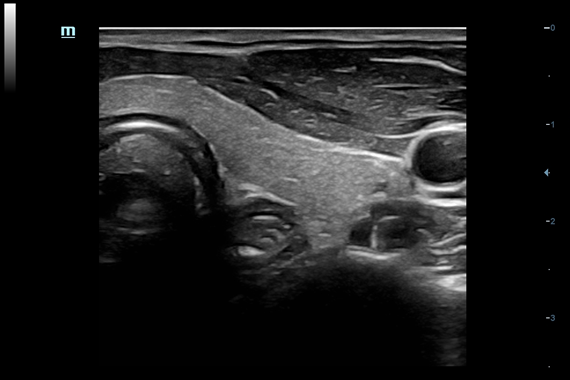

Система ультразвукового исследования Mindray DC-60 EXP X-INSIGHT является новейшей разработкой для проведения комплексных обследований на высшем уровне. Она обеспечивает решение самых сложных задач в таких областях, как кардиология, акушерство и гинекология, сосудистые заболевания, педиатрия и многие другие.

DC-60 EXP X-INSIGHT - это современный стационарный УЗИ-аппарат с функцией сенсорного управления и очищенной гармонической визуализацией, обеспечивающей лучшее контрастное разрешение и технологию 4D-визуализации. Он оснащен 21,5-дюймовым монитором, который может поворачиваться на 180 градусов, что удовлетворяет потребности врачей в качественной ультразвуковой диагностике.

• Smart FLC™ - режим автоматического оконтуривания, подсчета и определения размеров фолликулов из объемного изображения (необходим модуль 4D)

• Gynecology package - предустановленные параметры, аннотации, маркеры, программы измерений для гинекологии

• 3D/4D ректально-вагинальный датчик Mindray DE10-3E